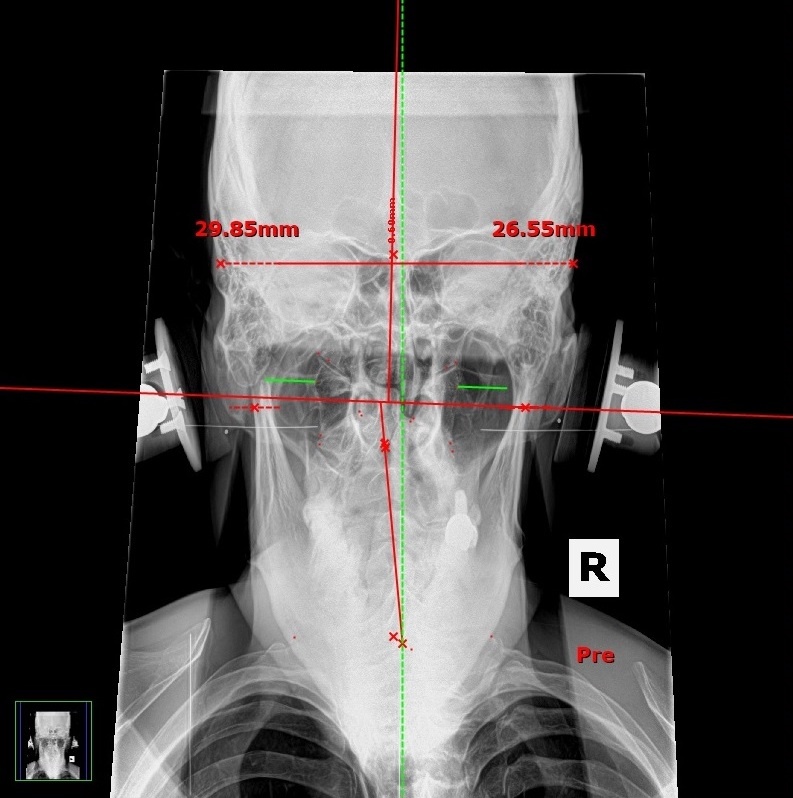

NUCCA Chiropractic Treatments to Fight Brain Inflammation

NUCCA to Lower Brain Inflammation

Dr Devin Young

When our head is out of alignment this can disrupt CSF flow and can affect our glymphatic system causing brain inflammation.

- Free NUCCA Assessment if you are in San Diego from Dr Devin Young